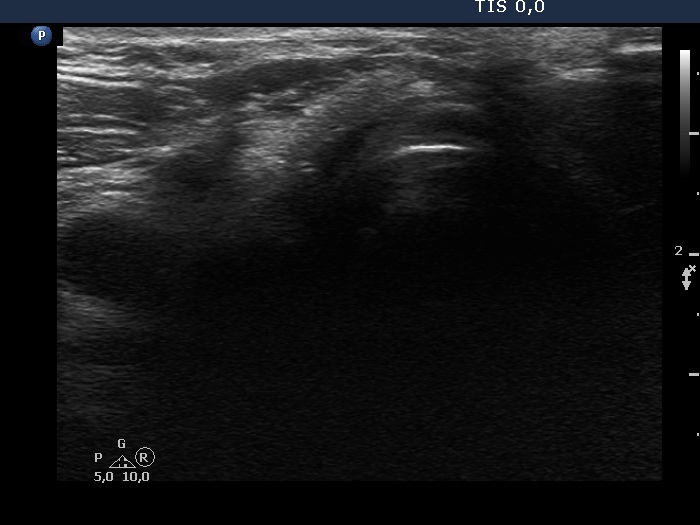

Eleven years after surgery (second and third rows of images):

Clinical data: The patient came to a follow-up. He told us that he decided not to visit the surgeon because the mass did not cause any complaints. He didn't remember exactly, but a few years ago he couldn't feel the knot at all, it had slowly disappeared on its own over the years.

Palpation: no abnormality.

Laboratory tests: TSH 3.56 mIU/L on daily 75 microgram levothyroxine.

Ultrasonography. The right lobe remained unchanged. Compared with the previous finding, a much smaller, inhomogeneous mass was found according to the left lobe. A few centimeters above and ventral to the left lobe, a cystic lesion was found within the strap muscle and close to this, an amorphous hyperechoic fragment was also present (see video).